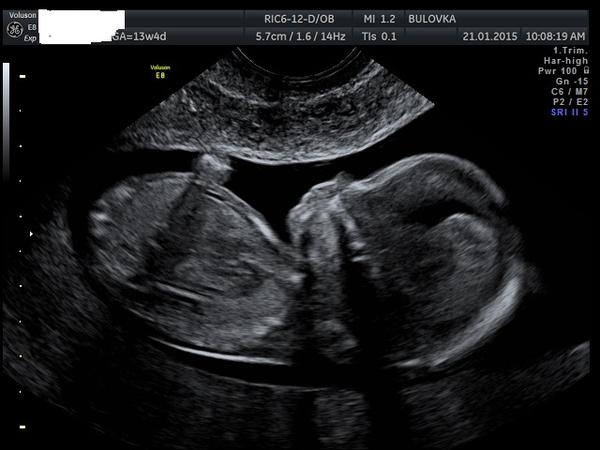

Děvčata, na NT srceeningu mi nechtěli říct pohlaví miminka, že prý to neříkají... vím, že je ještě brzo, ale hodně z Vás to v tomhle období už vědělo....Vidíte tam něco?

@ludul Podle té druhé fotky, vypadá to, jakoby se miminko horní polovinou těla přetáčelo do strany a nožičky ještě zůstaly v původní poloze, vpravo mi připadá, že to vypadá spíš jako ,,kávové zrno'' jak se říká, tedy na holčičku. Ale jo to absolutně amatérský tip 🙂

já zcela amatersky, bez jakýchkoli zkušenosti vidím pindíka, podle té první fotky ... nebo je to stín......tak uvidíme...

Podle první fotky to vypadá na holcicku...

To na co koukáme není ani edno rozkok, ale játra a odstup pupečníku. Takže vydrž. Na. Sice na NT řekli co to bude ale zatím nevěřím, je to oc malinké, takže ještě dva týdny a snad se to 100% dovóme.

Já myslim, že z tehle snímku to nikdo nepozná, protože neni videt mezi nožky🙂 Každopádne podle profilu obličeje bych tipla holčičku 😉